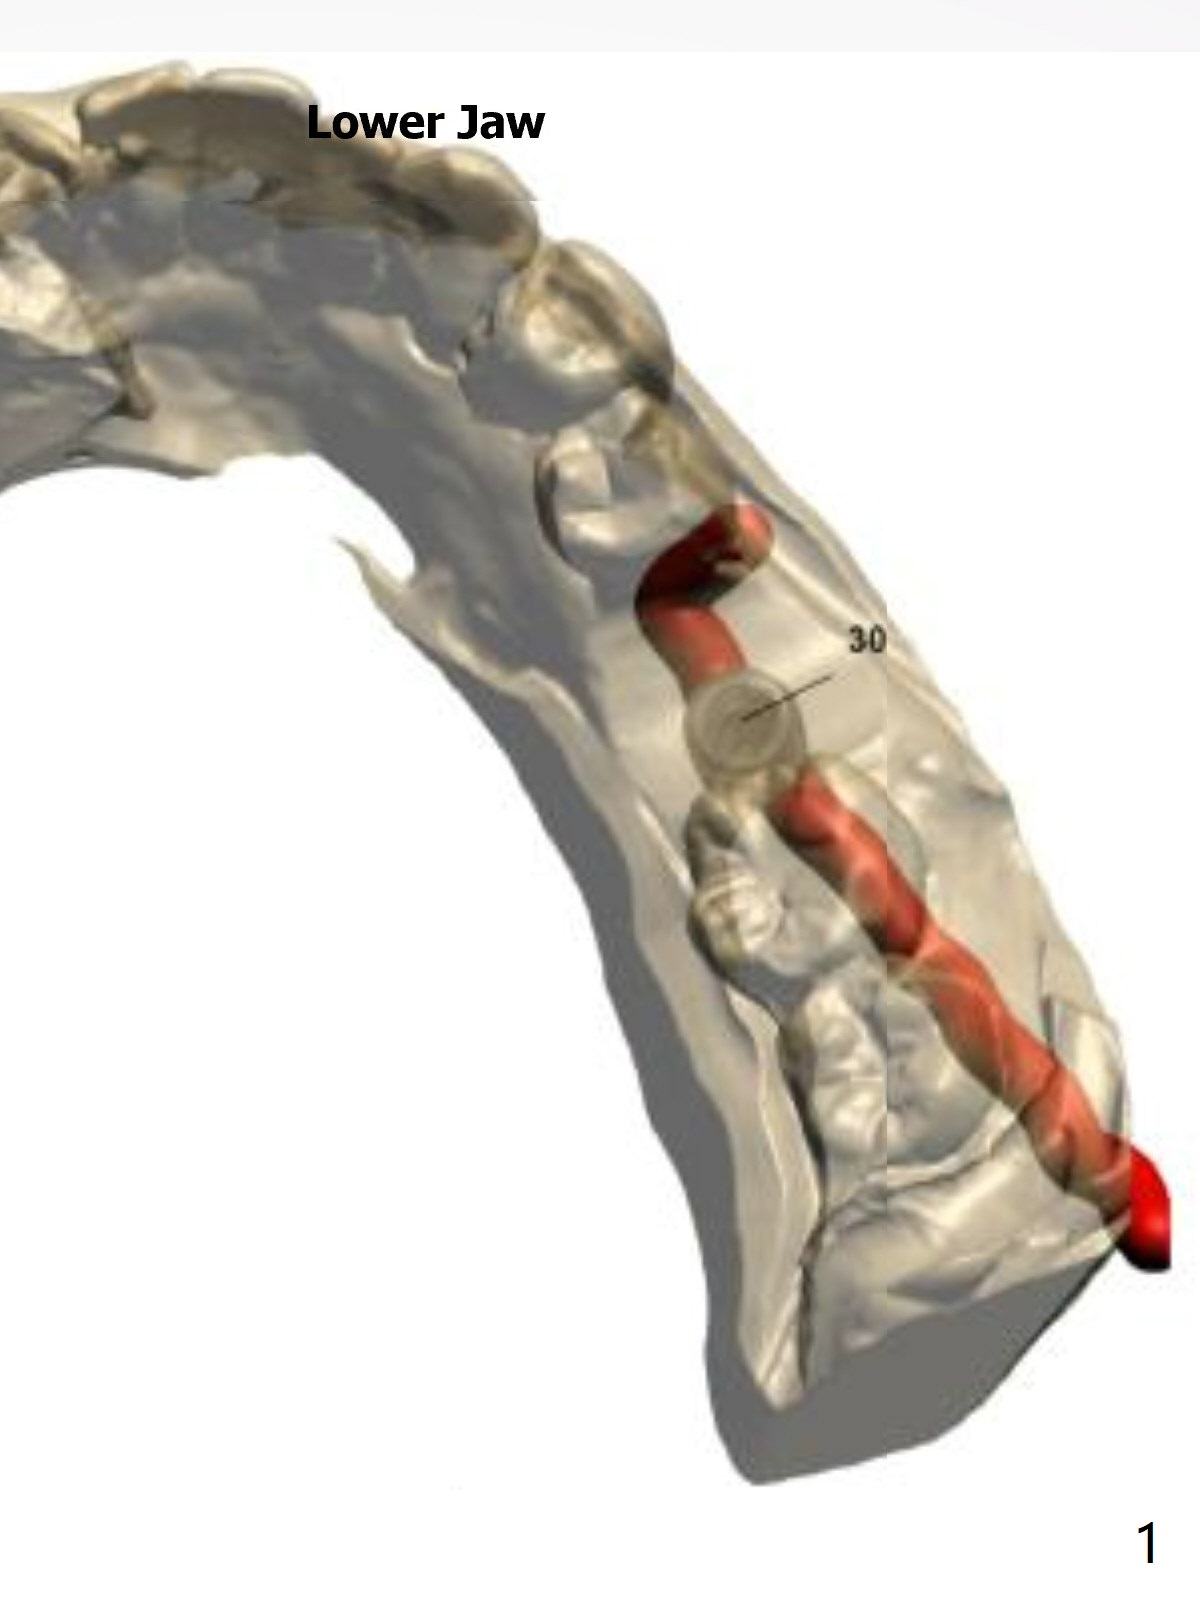

A short implant will be placed in association of a branch of the Inferior Alveolar Nerve.